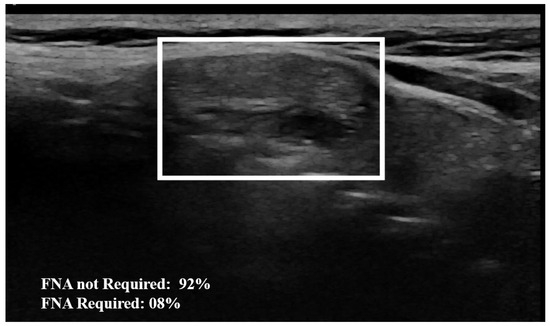

Examples of our method for the classification of the thyroid nodule images are shown in Figure 5 and Figure 6. The results of the proposed model with and without data augmentation are shown in Table 2. We can conclude that adding synthesized images improved the performance of the model quite effectively. We compared our proposed method with different deep learning architectures (Table 3). We began with experiments using a simple CNN and then fine-tuned pre-trained features to capture specific patterns relevant to our task. This approach led to improved performance compared to training a model from scratch. We conducted numerous experiments on the combination of focal loss parameters ( α and γ ) and different deep learning architectures. For our classification, α was set to 0.25 for the negative class and 0.75 for the positive class, depending on the class imbalance. Typical values for γ were in the range [ 0 , 5 ] . We experimented with several values of γ within this range for different models listed in Table 3, and γ = 3.5 was empirically found to be the optimal value.

The proposed method outperformed the other classic approaches. This is due to the fact that the incorporated attention modules are playing an efficient role in extracting the most important features. The other models did not perform well compared to the proposed approach, most likely due to over-fitting. We observed that the other models ended up memorizing some abstract patterns and were highly sensitive to random fluctuations. Hence, the lowest F1-score on this classification task was 0.79 , obtained from the predictions done by the simple CNN network. The proposed method only misclassified 4 images out of the 64 test set images, as illustrated by the confusion matrix in Figure 7. During the training session of the model, 20% of the dataset is automatically split for the validation process. We also assessed the model’s generalization capacity on unseen data. In the test set dataset, the model maintained high scores, achieving an average accuracy of 0.94 and a F1-score of 0.93 . These results indicate the robustness and effectiveness of the model’s performance in accurately classifying thyroid nodules. The model’s performance evaluation was conducted on individual image database centers to assess the portability of our approach. The average accuracy and F1-score for the test set from the Hospital of Bastia database were 0.87 and 0.89 , respectively. Similarly, for the test set from the Hospital of Dijon database, the average accuracy and F1-score were 0.90 and 0.86 , respectively. However, the mixed test set from both centers achieved the highest performance, with an F-score of 0.93 , as shown in Table 3. We also compared the proposed method with previous studies, as detailed in Table 4. The results demonstrate that our approach provides competitive performance in the classification of thyroid nodules, achieving high accuracy and reliability compared to other existing methods. For instance, in Figure 6, the probability of the nodule requiring FNA based on the model output is established to be 84%. Then, according to our model, this nodule is at high-risk level and fine needle aspiration is recommended.

Figure 5. Example of nodule classification: The AI model establishes a 92% probability from the image that the nodule does not require FNA, indicating that FNA is not necessary. The surrounding rectangle indicates the location of the nodule.